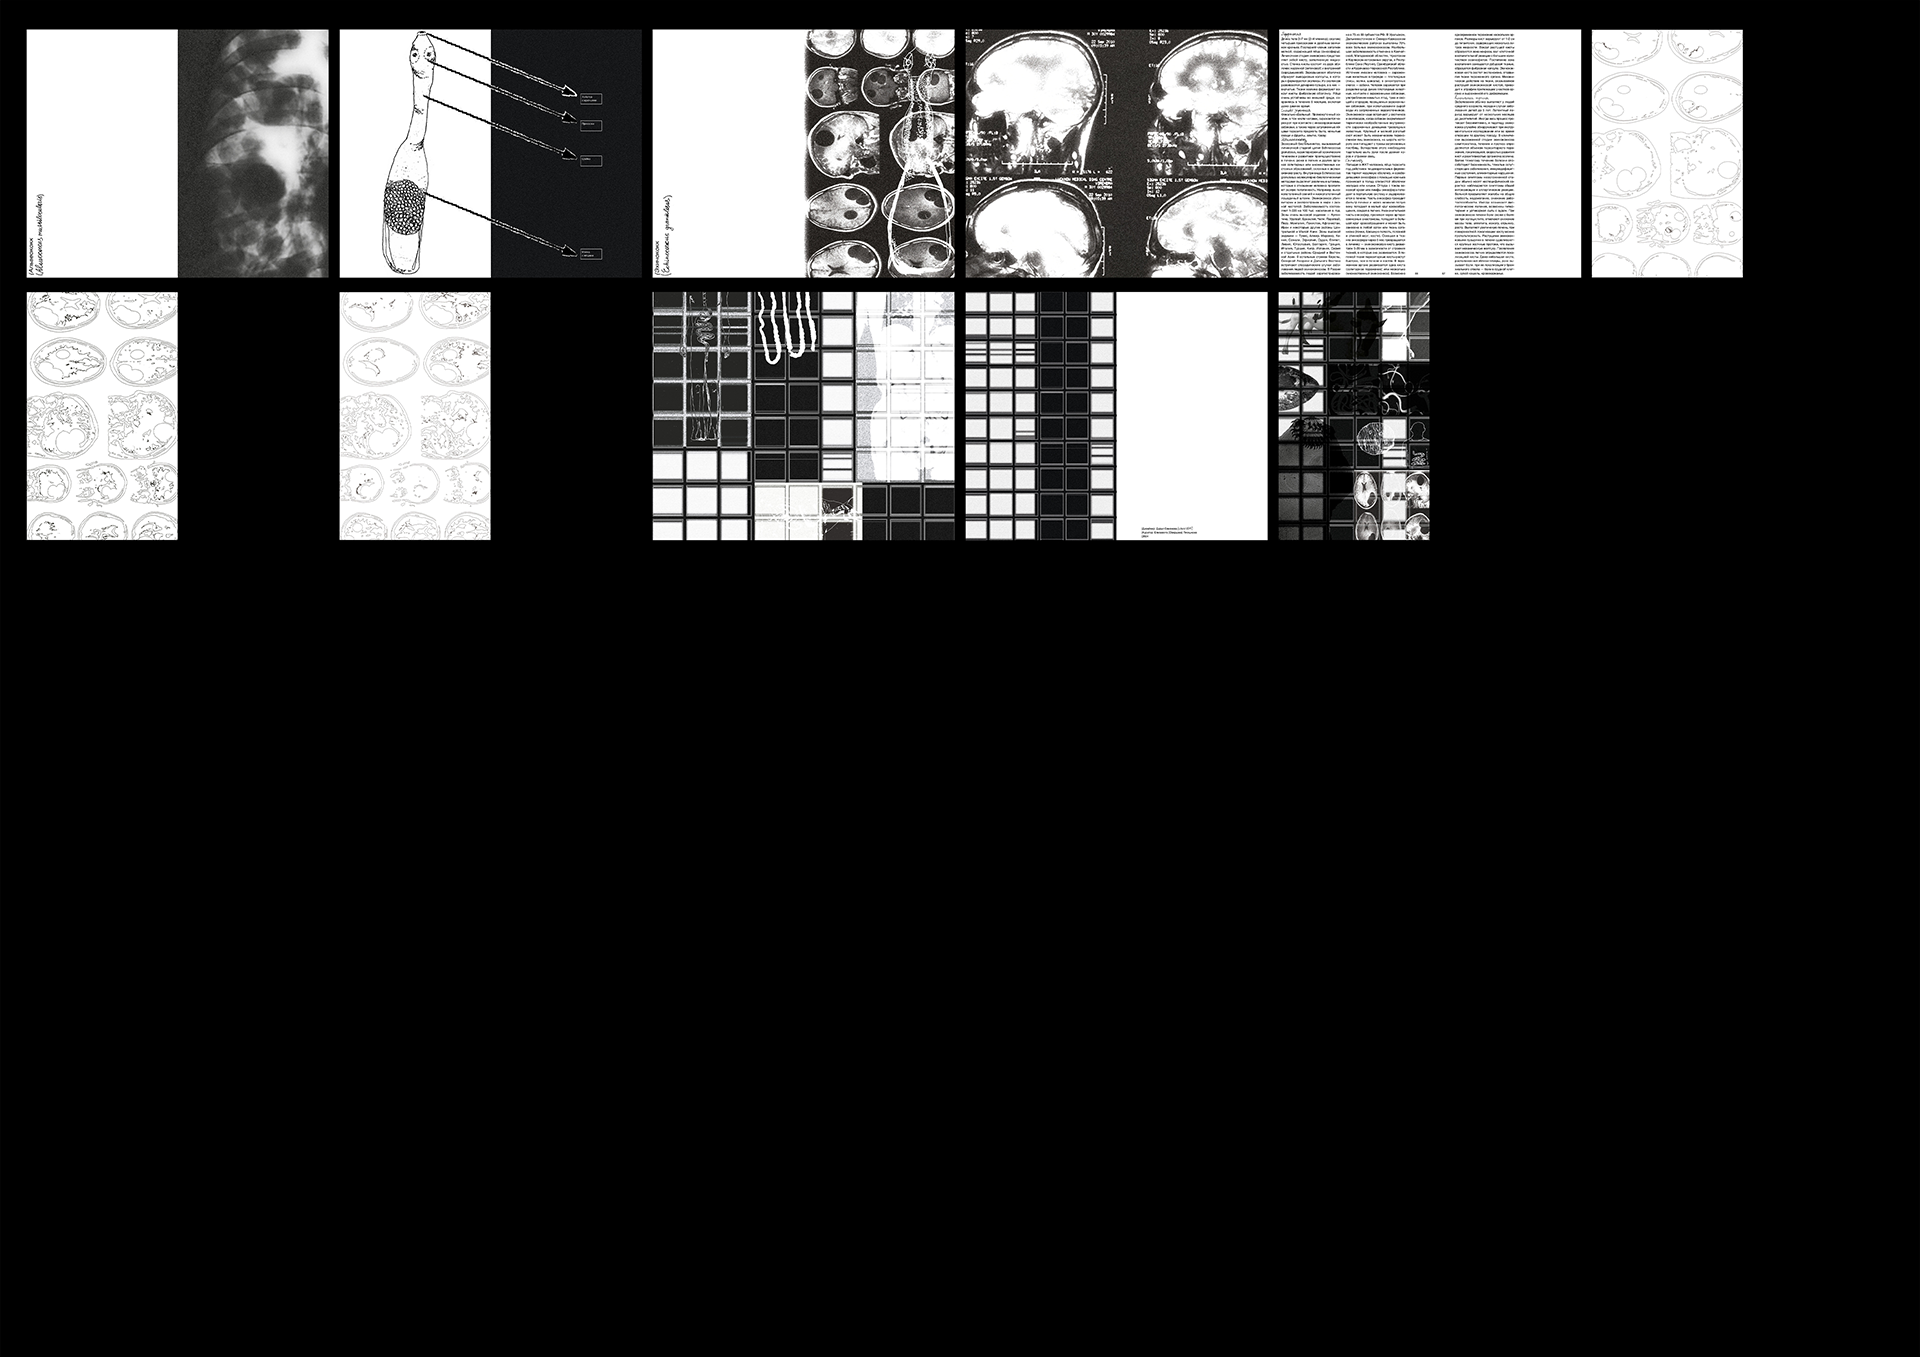

«Медицинская паразитология: Плоские черви» — компактный справочник, посвящённый паразитическим плоским червям, созданный под вдохновением от старых медицинских и биологических учебников. В рамках работы я переосмыслила дизайн таких изданий, сделав его смелее. Помимо самой книги, проект включает чехол для неё и конверт с иллюстрациями плоских червей на предметных стеклах.